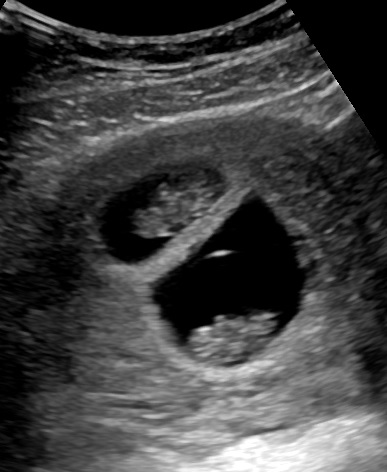

Gratulerer med 8 uker

Synes det er greit med ekstra UL til tvillingene jeg. Det å se på hvordan de ligger/hva de evt deler er lettest tidlig i svangerskapet. Koselig med en jordmor som forstår deg